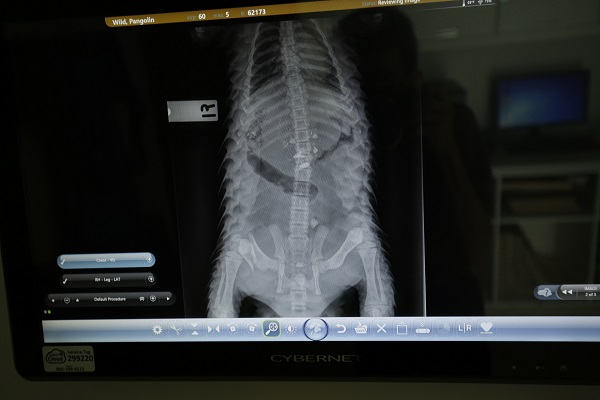

Dr Charlene Yeong, Manager, Conservation & Wildlife Health, examines an X-ray of Berani’s right femur, and concludes that the implants are stable and bone healing has been recorded.

Close-up of Berani’s X-ray taken on 28 Jan 2019 showing that the implants are in place and that bone healing has been recorded.